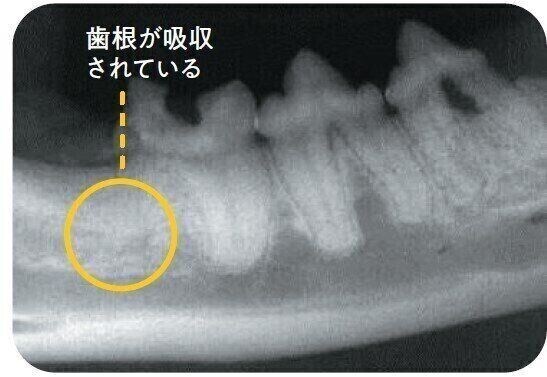

タイプ3

タイプ1とタイプ2が併発しているタイプ。1つの歯に2つの歯根がある場合、片方の歯根のみ吸収されている状態。写真の左端の歯は、左側の歯根のみ吸収され、骨と同化しています。